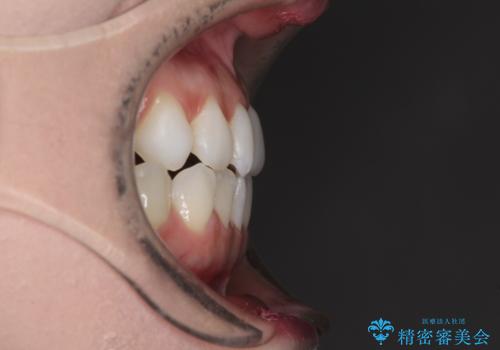

前歯のデコボコをすっきりと インビザライン矯正

- 前歯のデコボコを治したいとのことで来院された患者様です。

下顎が前方位にある方であったため、下顎の歯列全体の後方移動とIPR(歯と歯の間を削る)によってデコボコが解消するように設計し、インビザラインにより治療を行うこととしました。